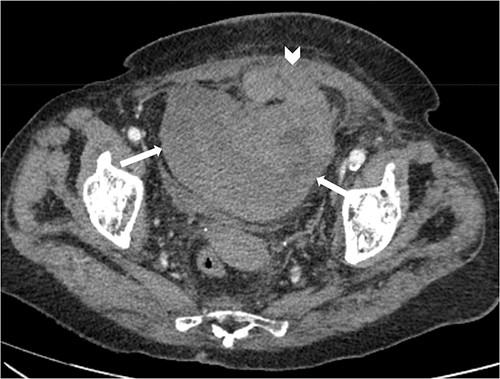

Suspecting internal haemorrhage, contrast-enhanced computed tomography (CECT) of the abdomen and pelvis was arranged. The CT images showed the presence of multiple haematomas with evidence of active bleeding (Figs 1 and 2).

Axial non-contrast and post-contrast (100-s delay) CT abdomen and pelvis slices demonstrating two further left abdominal wall and pre-peritoneal collections (white arrows) with high attenuation on non-contrast slices (A and C) in keeping with haematoma. There is contrast blush in two locations (white chevrons in B and D) in keeping with active bleeding. The vascular territories that have likely contributed to bleeding include branches of left inferior epigastric and left lumbar arteries.